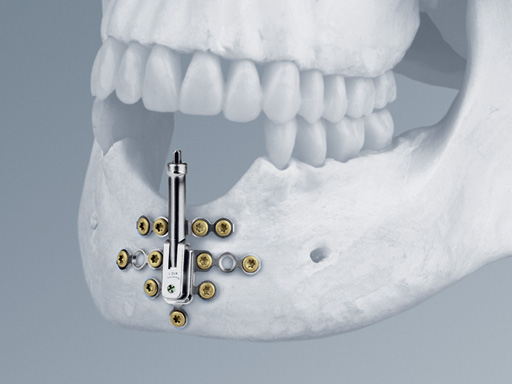

One of the main features of the Alveolar Distractor is its vector adjustability: an angulation mechanism allows easy intraoperative selection of the distraction vector. Therefore, extensive adaptations to the foot plates can be avoided. The distractor can be angled up to 52 toward the buccal and 32 toward the lingual side. After adjusting the vector, the angulation mechanism must be relocked by tightening the fixation screw.

The rigid base plate, with optional screw holes next to the angulation mechanism, allows safe anchorage of the distraction device in the residual bone segment. This leads to high stability ensuring rigidity and preventing potential unfavorable distraction vector changes due to soft-tissue pull.

Three different implant sizes allow for 8 mm, 12 mm, and 16 mm of distraction. This choice offers the flexibility to fit the distractor to different anatomical conditions. To achieve the desired distraction result, the two bodies are connected with a pin to change the plane angle of the bone plates in one dimension. The angulation mechanism allows for fixation of this angle. This feature allows for a single, individual intraoperative adjustment of the distraction vector and addresses the importance of a correct distraction vector in a sagittal plane.

The plate is extended vertically to improve the vertical stability of the system helping to withstand lingual and palatal soft-tissue tension and therefore also guarantees a stable distraction vector. This device has housing for the distraction body to prevent soft-tissue irritation as there is no exposure of the surrounding soft tissue to the threaded rod during distraction and latency.